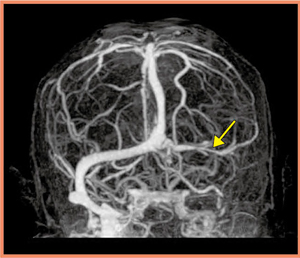

通常の単純撮影と造影CTの画像(図5)では,MRI以上の情報は認められないが,ボリュームキャンでCTA(図6)を行ったところ,左横静脈洞からの頸静脈にかけて,順行性の血流がないことが確認できた(↓)。CTを行うことにより,静脈性の梗塞という診断を確定することが可能になった。その後,保存的に加療され,1年経過した現在も患者の予後は良好である。

図6 症例のAquilion ONEによるCTA画像